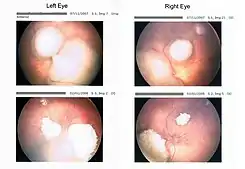

![]() Tumores del retinoblastoma tomados con un "retinoscan" antes y durante la quimioterapia. | ||